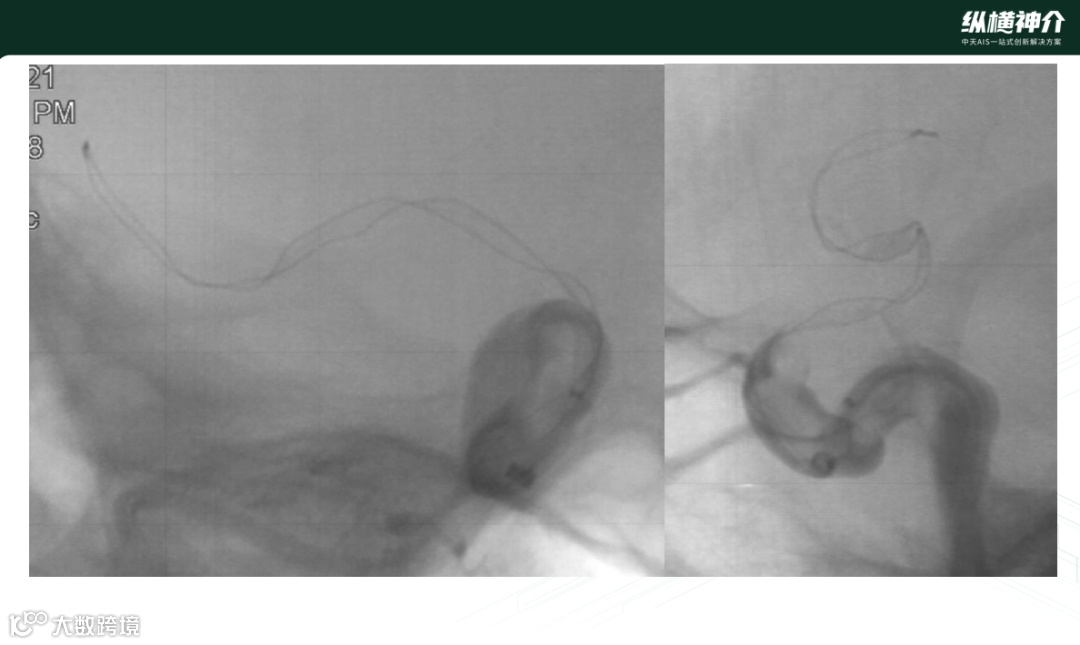

病例二

• 天弋®取栓支架 6*40mm 4*30mm

• 微导管在到达远端后,造影发现M2处也有血栓存在

• 天弋® 6*40mm取栓支架到位释放打开,显影性非常好,相比其他尺寸,对大负荷量血栓具有优势

• 天弋®取栓支架从近端到远端是缠绕血栓,而没有被近端血栓刮除掉

• 二次取栓操作,大脑中和颈内动脉血栓进一步减容

• 第三次取栓

• 天弋®取栓支架 4*30mm

• 抓捕的血栓效果来看,血栓是一个旋转的形态,用手去取下支架上的血栓比较难以取下,需要把血栓碾碎后取下。支架与血栓粘结非常紧密,临床表现优异